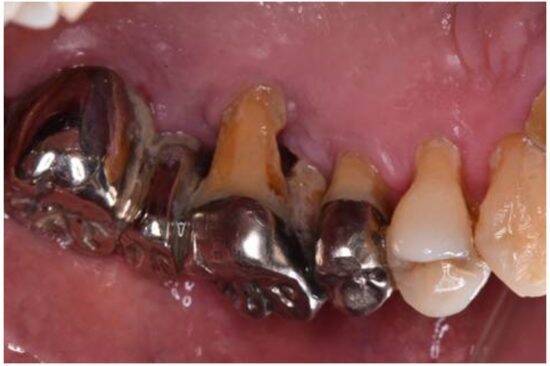

一方、歯の管理が悪い人は、神経に到達するような重度のむし歯、歯周病から、被せ物やブリッジ、抜歯、インプラントや入れ歯になるなど、治療が高額化していきます。

それなのに、お金をかけた分、生まれ持った元のお口よりキレイに機能的になっていくわけではないのです。通院回数を比較しても、治療箇所が多くなればなるほど、時間もお金も取られてしまいタイパが悪くなります。

保険診療のクオリティは、やはり自費診療には敵わず、銀歯の下でむし歯が再発する「二次カリエス」のリスクや、見た目年齢への影響もあります。